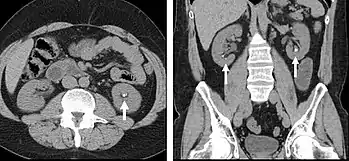

Unenhanced CT

Non-contrast CT scans Figure 1a (left) and 1b (right) are of limited use for the differentiation of soft tissue structures. However, materials like blood, calcium (renal stones, vascular atherosclerosis), bone, and pulmonary parenchyma are highly visible and can usually be adequately assessed with non-contrast CT. For example, in the abdomen and pelvis, there are several indications for non-contrast imaging. These include: evaluation of renal calculi; assessment for gross intra-abdominal hemorrhage; and post-endostent volume measurements. In addition, non-contrast images are often obtained in conjunction with contrast enhanced images in evaluating potential renal transplant donors and in the evaluation of the pancreas (in combination with contrast phases). Of note, dual-energy CT and the development of virtual “non-contrast” images may ultimately obviate the combination scans. Additionally, CT angiography examinations performed for pathologies like aneurysms and dissection are frequently performed in conjunction with non-contrast imaging. The non-contrast images facilitate the differentiation of active extravasation or acute bleeding from vascular calcifications.